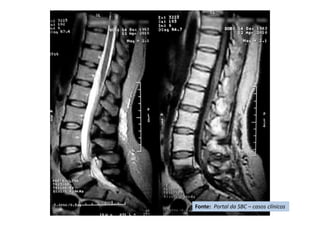

• Cifose pós-traumática

• Resumo do caso: Queda da própria altura com diminuição de força de

membros inferiores de forma gradativa.

• Paciente (dados): Sexo feminino, 54 anos

• História: Queda da própria altura durante internação hospitalar em outro

serviço para tratamento de crise de ativação do LES há 6 meses. Apresentou

diminuição de força de membros inferiores de forma gradativa. Foi avaliada

no serviço de origem e realizado TC e aventada a hipótese de mielite

transversa. Foi encaminhada ao CRER para reabilitação. Nesse momento

apresentava apenas parestesia em MMII e FM grau 0 (ASIA B).

• Diagnóstico(s): Consolidação viciosa de T5, com cifose pós-traumática e

compressão medular (ASIA B)

• Antecedentes de Lúpus (LES), uso crônico de corticóide e tabagismo severo

• Tratamento(s): Realizada vertebrectomia com descompressão medular e

reconstrução com Mesh CAGE e artrodese de T2 a T8 por via posterior.

• Seguimento ("Follow up"): PO 1 ano com boa melhora funcional da

paciente.

• Resultado Final: Paciente apresentou melhora gradativa da força muscular e

da função, estando hoje com força muscular grau IV em MMII, conseguindo

deambular e inclusive subir e descer escadas com apoio (ASIA D).

Fonte: Portal da SBC – casos clínicos

RM - corte sagital de

imagem ponderada em T2

com supressão de gordura

imagem ponderada em

T2